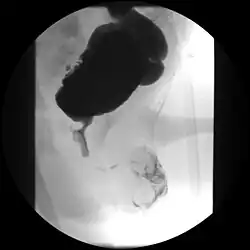

A paraplegic patient with neurogenic bladder on regular ultrasound follow-up showing thickened bladder wall with trabeculations and sediments within the bladder.

Ultrasound imaging can give information on the shape of the bladder, post-void residual volume, and evidence of kidney damage such as kidney size, thickness or ureteral dilation.[12] Trabeculated bladder on ultrasound indicates high risk of developing urinary tract abnormalities such as hydronephrosis and stones.[13] A voiding cystourethrography study uses contrast dye to obtain images of the bladder both when it is full and after urination which can show changes in bladder shape consistent with neurogenic bladder.[12]